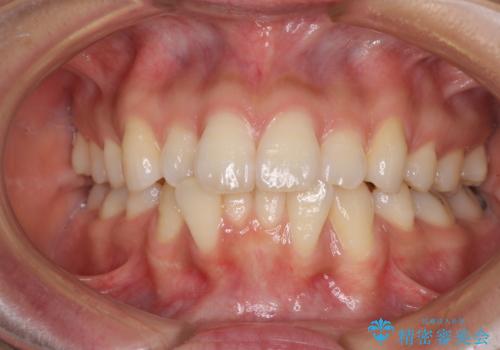

- 以前の矯正治療の後戻りにより、上下の前歯がでこぼこになってしまったことを気にして来院された患者様です。

口元がこれ以上突出することなく前歯の叢生が改善できるよう、歯と歯の間を削ってスペースを獲得し、インビザラインを用いて整えていくこととしました。

目安の装着時間である1日22時間をしっかりと実践してくださり、半年強という短期間で治療を終えることができました。